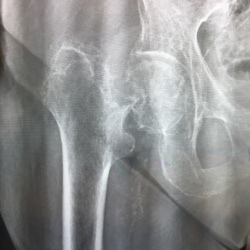

Коллеги, здравствуйте! Женщина, 80, боли в коленных суставах. Смущает зона в левой бедренной кости. Склероз и на фоне него овальное просветление. С другой стороны такого нет. Остеоид-остеома? Или...